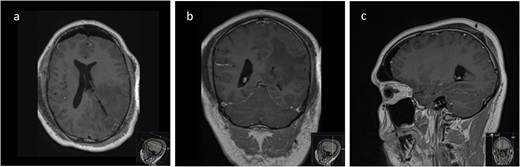

We hereby present the case of a 32-year-old gentleman referred to the neuro-oncology service with an 8-months history of left sided headaches, dizziness, and blurred vision. MRI head demonstrated a 50 × 52 × 51 mm lesion in the posterior horn of the left lateral ventricle, with extension into the periventricular white matter (Fig. 1). Following multi-disciplinary discussion, a plan was made for the patient to undergo a minimally invasive approach for resection of this lesion. Pre-operative cortical and subcortical mapping was performed with navigated transcranial magnetic stimulation (nTMS) and diffusion tensor imaging (DTI). The best trajectory was defined taking into consideration the localization of the cortico-spinal tract (CST, red), the inferior fronto-occipital fasciculus (IFOF, green) and the optic radiations (OR, yellow) (Fig. 2).

Pre-operative axial (a), coronal (b), and sagittal (c) T1-weighted post contrast MRI sequences demonstrating the avidly enhancing lesion in the posterior horn of the left lateral ventricle, with extension into the periventricular white matter.